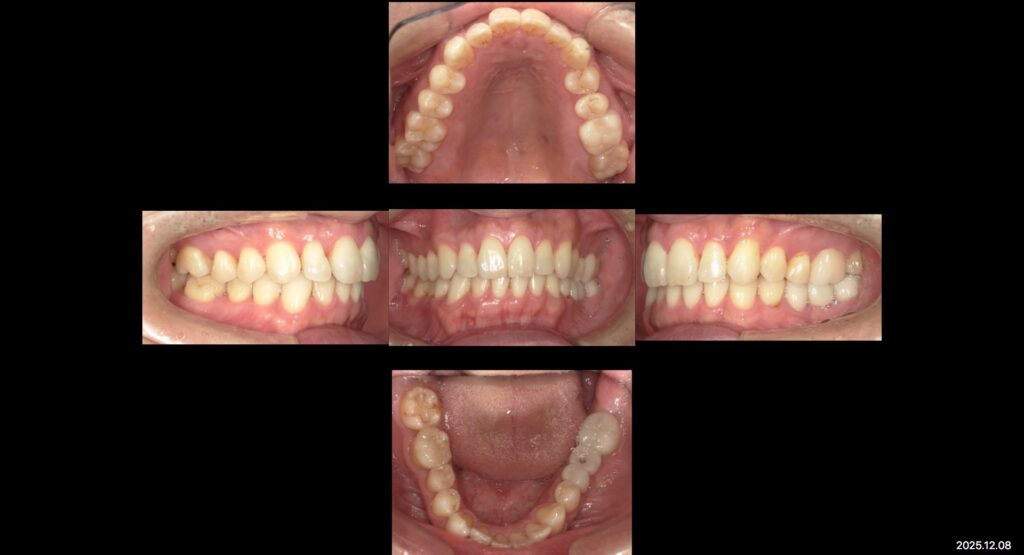

症例写真ー全顎治療ー

下:治療後口腔内写真

治療内容

矯正治療+補綴治療+インプラント+ホワイトニング

年齢

44歳

性別

男性

目的

欠損部治療と不適合補綴物のやり替えを咬み合わせ改善、審美や歯並びの見た目の改善

矯正治療や、虫歯治療、不適合補綴物のやりかえなど全顎的に根本治療を行いました。

現在は、ホワイトニングもしていて、メインテナンスに通っていただきながら経過観察を追っています。